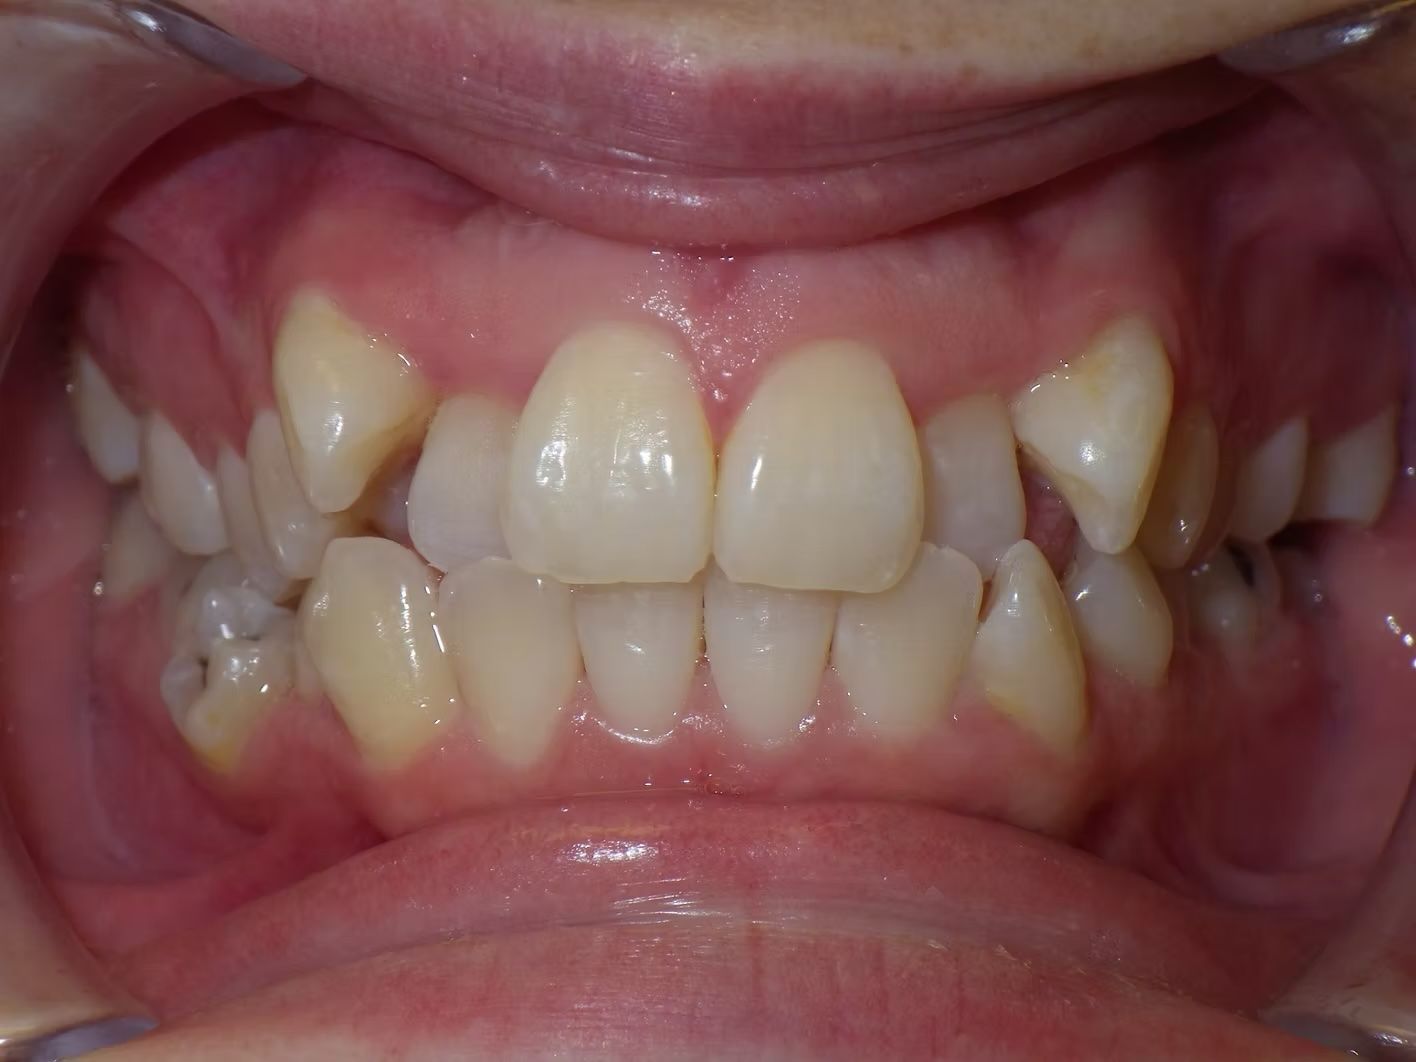

Fatima

Fatima didn't like her teeth. She was severely crowded in the top and lower dental arches. Her upper midline was off to the left. We extracted 4 teeth and lined up her teeth beautifully, corrected her bite and centered the upper and lower teeth with the face and each other.